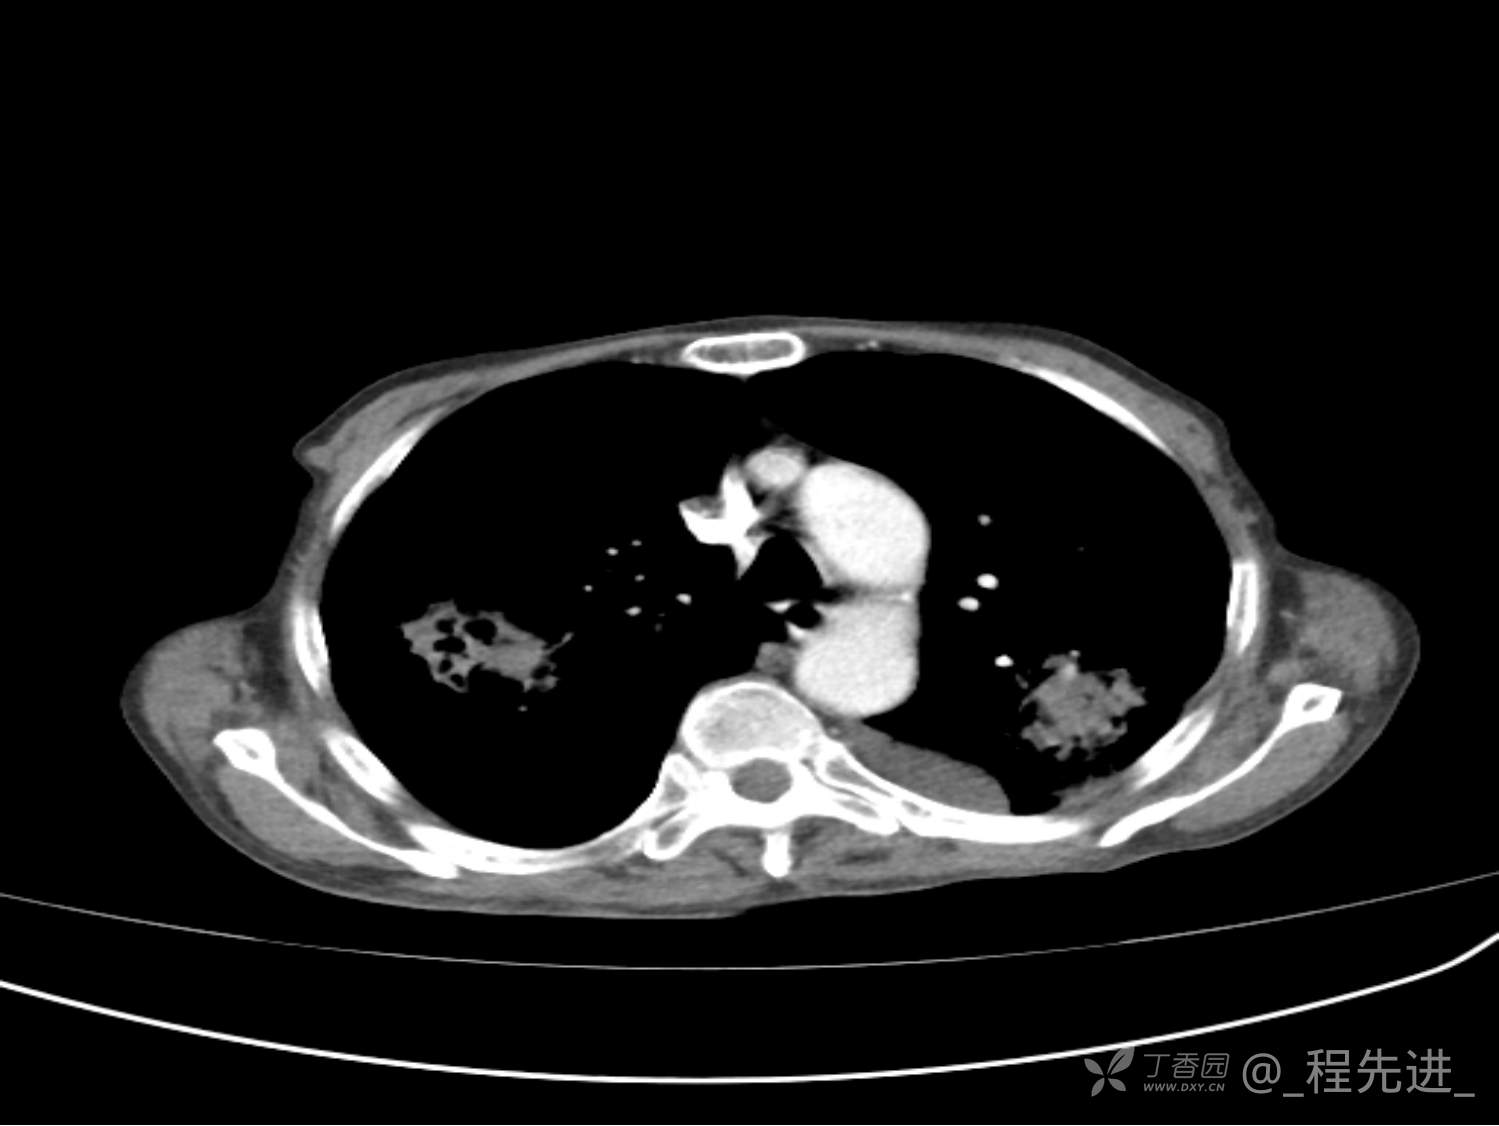

患者性别:男

患者年龄:81岁

简要病史:反复咳嗽、咳痰20余年,加重1周。两肺呼吸音低,可闻及散在干湿啰音。